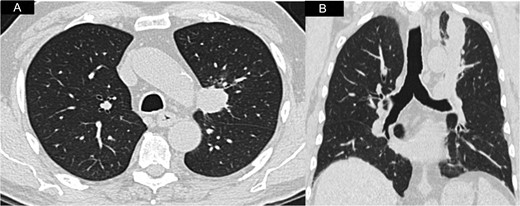

An 81-year-old man presented with a 2-month history of persistent cough and an abnormal chest x-ray showing a left upper lobe opacity. He was an ex-smoker and his past medical history was significant for hypertension, type 2 diabetes mellitus, and kidney cancer treated by radical nephrectomy 37 years earlier. Evaluation with [18F]-fluorodeoxyglucose-positron emission tomography/computed tomography revealed a large hypermetabolic peri-hilar left upper lobe lung neoplasm, in close proximity with the left main pulmonary artery (Fig. 1). No other lesions were detected elsewhere. Bronchoscopic citology brush was consistent for non–small-cell lung cancer and neoplastic involvement of mediastinal nodes was ruled out with endobronchial ultrasound. Global spirometry with transfer factor for carbon monoxide, echocardiogram and laboratory tests results were unremarkable. The patient was therefore deemed suitable for surgical resection. A left pneumonectomy and mediastinal nodal dissection was thus performed via a standard postero-lateral thoracotomy. Recovery after the operation was uneventful and the patient was discharged on post-operative Day 5. The histopathology findings were however significantly surprising. The tumour cells presented in solid islands and sheets, with distinct cytoplasmatic membranes, mild to moderately pleomorphic nuclei often with ‘raisinoid’ appearance and occasional binucleate cells. The cytoplasm was abundant and largely clear (Fig. 2). In view of the striking cytoplasmatic clearing, immunohistochemistry was also performed. The tumour cells were negative for CK5/6, p63, TTF-1, CD10, while there was a strong positivity for CK7 (Fig. 3) and CD117 (Fig. 4). The final diagnosis was therefore metastatic RCC, which had relapsed after the remarkably long period of 37 years, which is, to the best of our knowledge, the longest ever reported interval between surgery for RCC and the occurrence of a pulmonary metastasis. At 3-year follow-up, the patient is well and no recurrence of disease has been observed.

A and B Axial and coronal CT-scan view showing the left peri-hilar lung mass in close proximity to the main pulmonary artery.